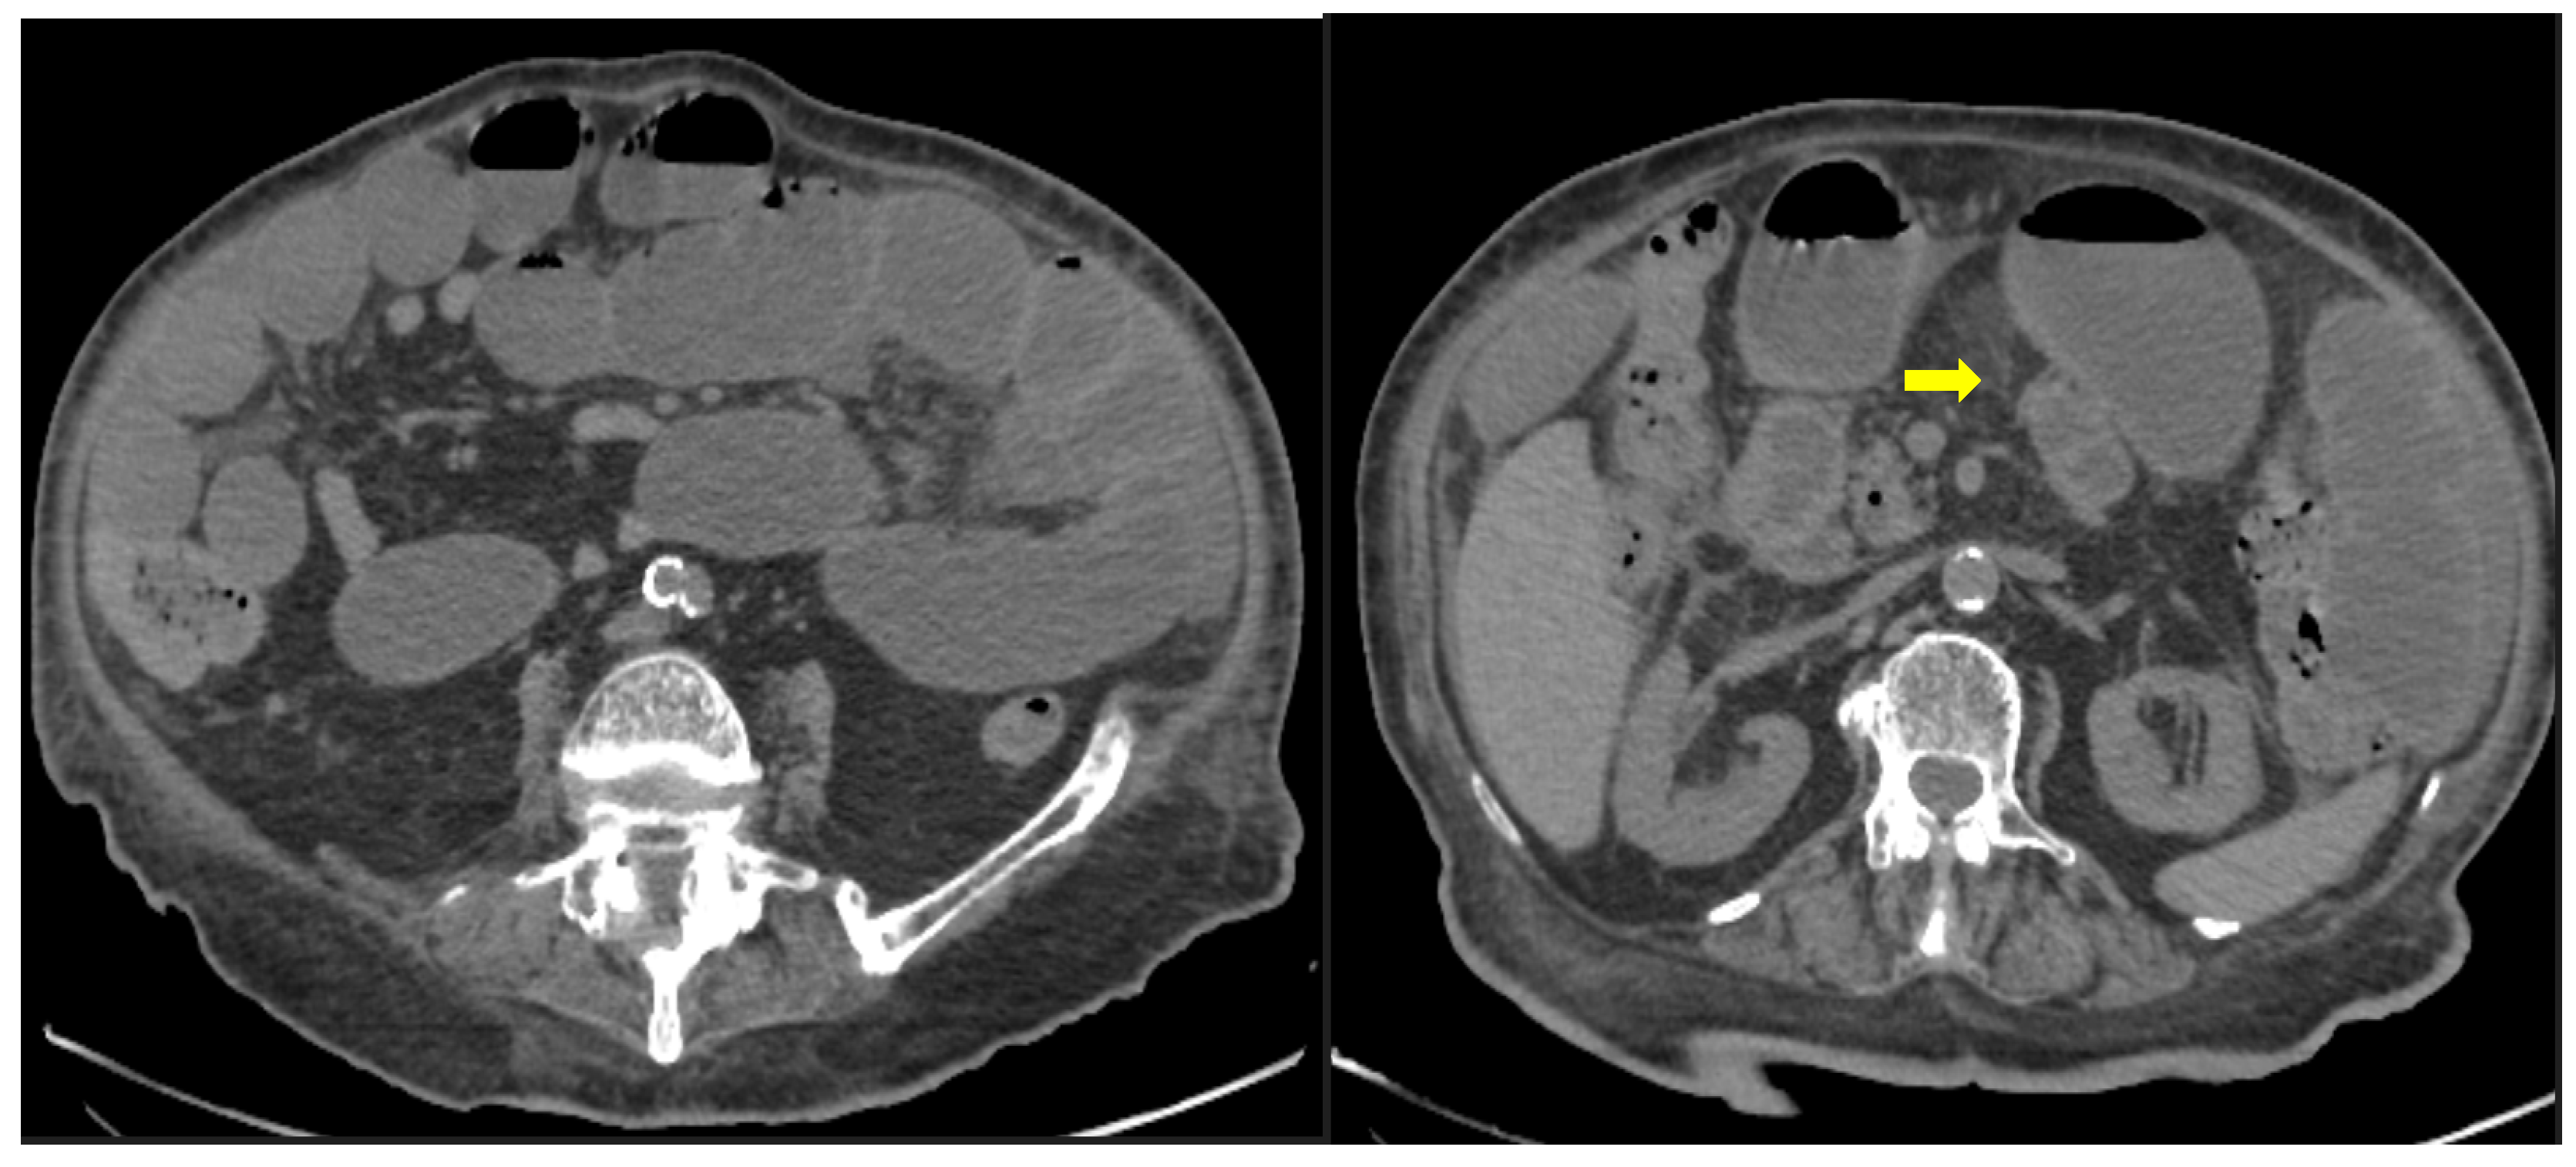

Figure 10. 56-year-old hospitalized male patient with COVID-19 pneumonia with raised level of d-dimers. CT depicting the thrombosed portal vein (yellow arrow). Note that in the same scan, there is extended small bowel thickening with mesenteric free fluid.